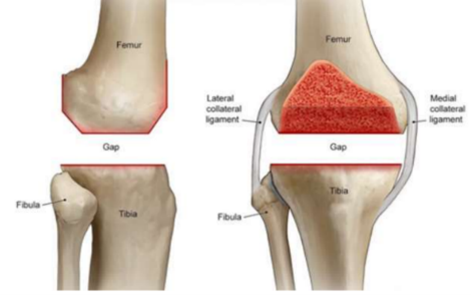

Artros – Ledsvikt. Vad är artros? Hur ser friskt ledbrosk ut?

• Ledbrosket sviktar (uppluckrat)

• Ökad friktion

• Sämre dämpning

• Inflammation och smärta

Friskt ledbrosk ska set ut som en kokonött i genomskärning